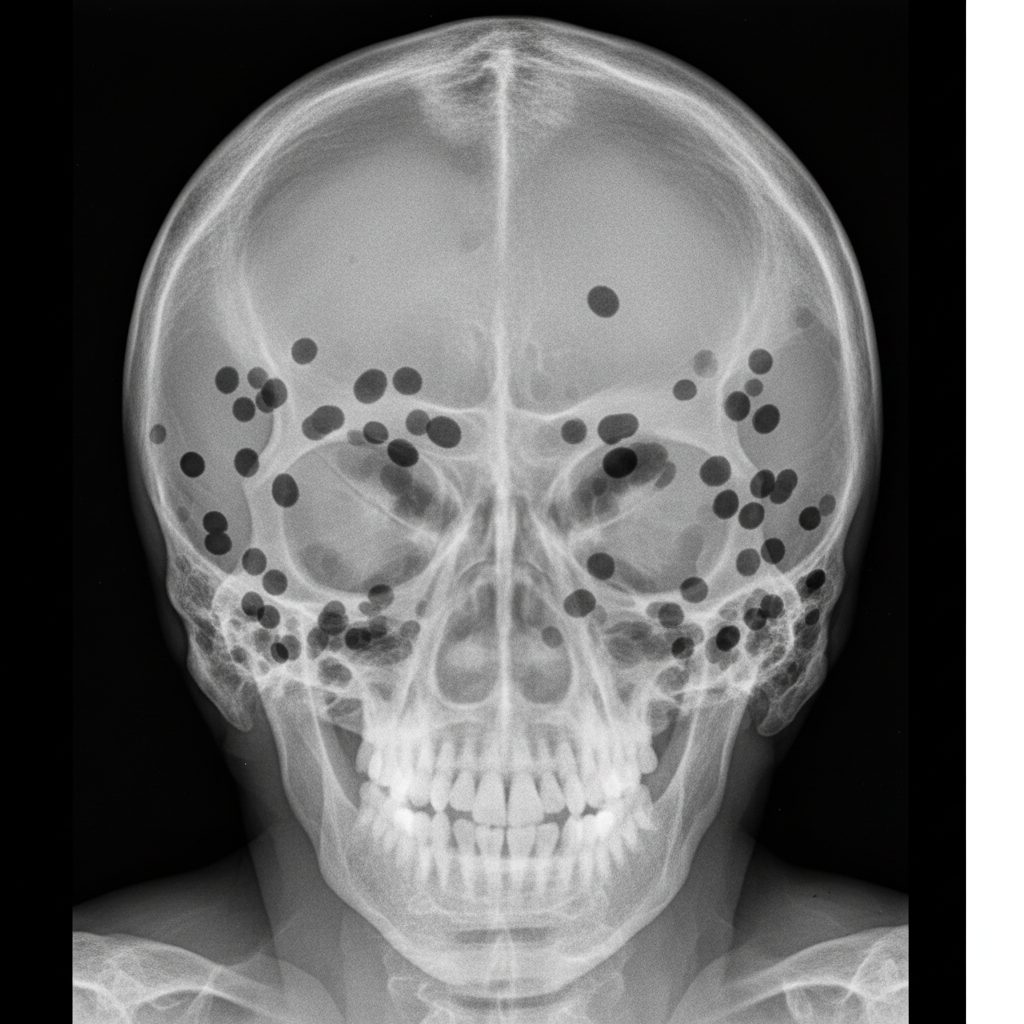

A 60-year-old man presents with bone pain and fatigue. His skull X-ray is shown in the image. This appearance is most suggestive of which of the following conditions?

Explanation: ***Multiple myeloma*** - **Punched-out lytic lesions** (raindrop skull or Swiss-cheese appearance) in a 60-year-old with bone pain and fatigue is classic for multiple myeloma. - **Plasma cell malignancy** commonly causes **hypercalcemia**, **anemia**, and **renal dysfunction** along with characteristic skull lesions. *Eosinophilic granuloma* - Typically presents as a **single well-defined lytic lesion** with **beveled edges** rather than multiple punched-out lesions. - More common in **children and young adults**, not elderly patients with systemic symptoms. *Hyperparathyroidism* - Causes **pepper-pot skull** or **granular osteoporosis** with diffuse bone resorption, not discrete punched-out lesions. - Associated with **elevated calcium** and **PTH levels**, but lesions appear more diffuse and granular. *Acromegaly* - Results in **bone enlargement** and **thickening** due to excess growth hormone, not lytic destruction. - Skull shows **frontal bossing** and **enlarged sinuses**, opposite of the destructive lesions seen here.